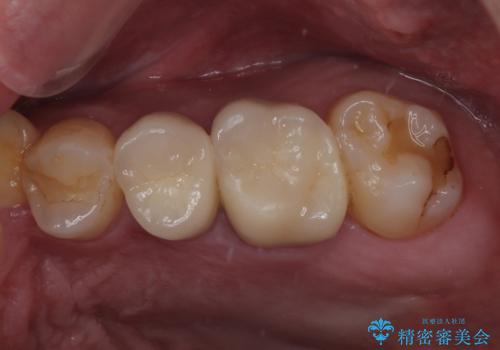

左下にフロスを通すと引っかかる オールセラミッククラウン

担当医 有澤哲郎